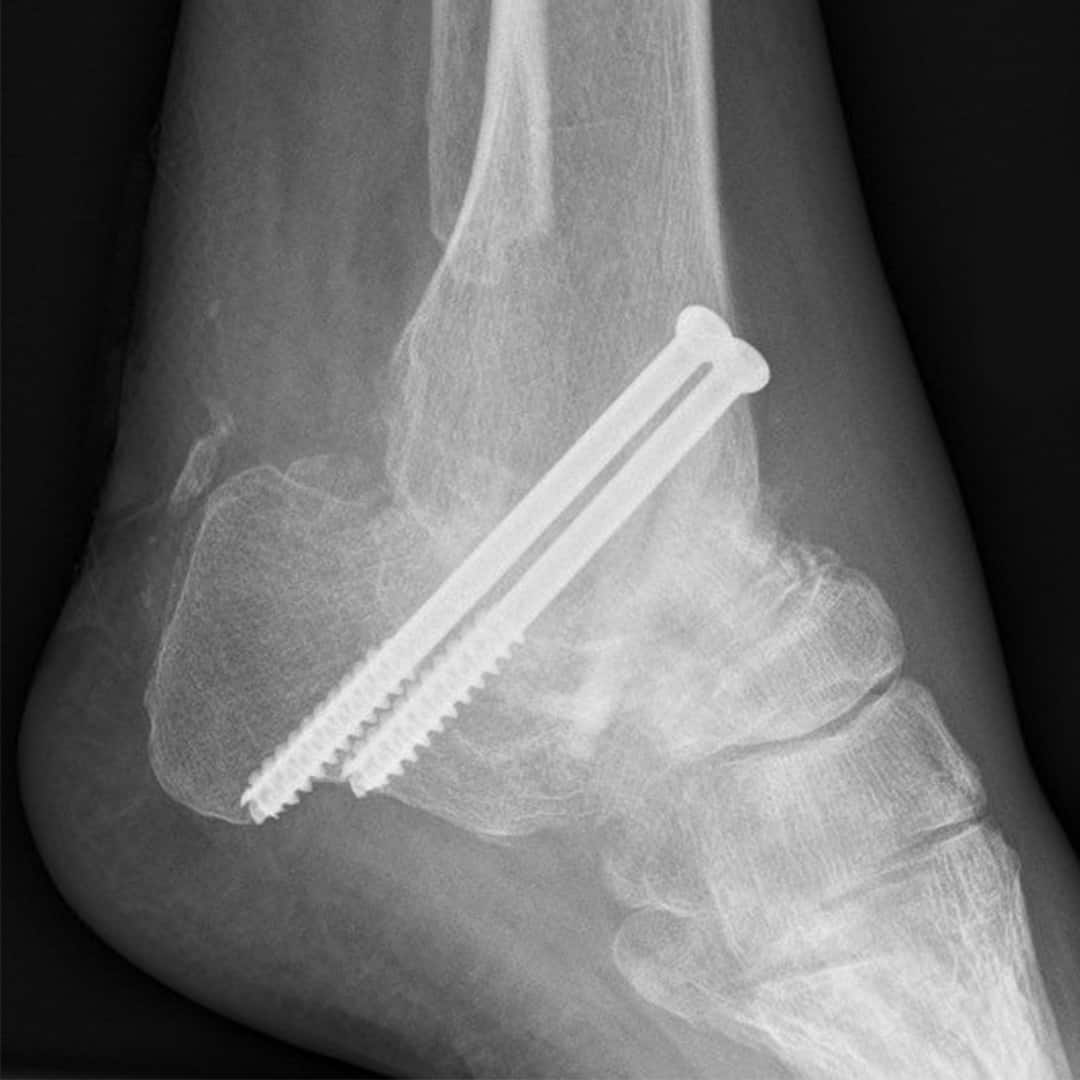

Bild einer OSG & USG Arthrodese mit zwei Metallschrauben 3 Monate nach der Operation. Freundlich zur Verfügung gestellt von Prim. Dr. Norbert Freund.